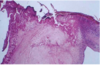

Fibrinous Pericarditis

- Shows thin strands of fibrinous exudate that extend from epicardial surface to pericardal sac

Fibrinous Pericarditis

Surface appears roughened from normal glistening appearance by strands of pink-tan fibrin

Fibrinous Pericarditis

Epicardial surface of heary shows shaggy fibrous exudate. “Bread & butter” pericarditis.

Fibrin often results in finding on PE of friction rub as strands of fibrin on epi/pericardium rub against each other

Microscopically, pericardial surface shows strands of pink fibrin extending outward w/ underlying inflammation.